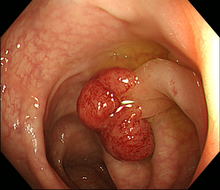

図 大腸がん

肛門から大腸に内視鏡を挿入して大腸内を直接調べる検査です。大腸内に便が残っていると十分な観察ができません。前日から食事制限が必要で、検査当日には腸管洗浄液を1〜2リットル飲み、腸管内をきれいにしてから検査を行います。通常検査は10-20分程ですが、検査には多少の苦痛を伴うため、当院では希望される方には鎮静剤を使用して検査を行っています。大腸内視鏡検査では、大腸がんや大腸ポリープを見つけることができます。

1)内視鏡的ポリープ切除術(ポリペクトミー)

大腸に隆起したポリープを認めた場合、ポリープの茎の部分に、内視鏡を通して通電ワイヤー(スネア)を掛け、ポリープを締め上げて高周波電流で切除します。高周波で切除することにより、切除した部位に熱凝固という作用が起きて止血できます。大腸粘膜には知覚神経がないため切除時には痛みは感じません。ポリープの大きさや形状によって1日から数日間の入院が必要です。